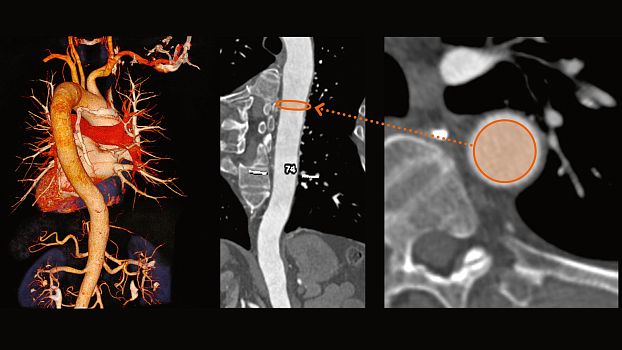

Клинические изображения

SOMATOM go.Up - компьютерный томограф для проведения рутинных и целевых осмотров, лучевой терапии и ангиографии. Система отличается инновационным дизайном рабочего места и полностью обновлённой концепцией сервиса, которая способствует снижению расходов по эксплуатации. Подходит для обследования головного мозга, легких, толстой кишки, сердца, сосудов. Вы можете заказать или купить со склада в наличии компьютерный томограф Siemens SOMATOM go.Up по выгодной цене, от надежного официального дистрибьютора "МСТ", с бесплатной доставкой в любой город по всей России.

SOMATOM go.Up позволяет расширять клинический диапазон и развиваться, достигая существенных результатов. Благодаря использованию высоких технологий система обеспечивает результаты, которые ранее были доступны только на томографах высокого класса. Кроме того, SOMATOM go.Up хорошо подходит для целей лучевой терапии. Благодаря пакету RT Image Suite, установленном на рабочей станции сбора данных, можно без труда выполнять разметку, оценивать изображения и проводить оконтуривание мишеней для лучевой терапии.

SOMATOM go.Up позволяет проводить высококачественные ангиографические исследования сосудов с хорошим контрастным усилением, субмиллиметровыми срезами и точной синхронизацией по времени.